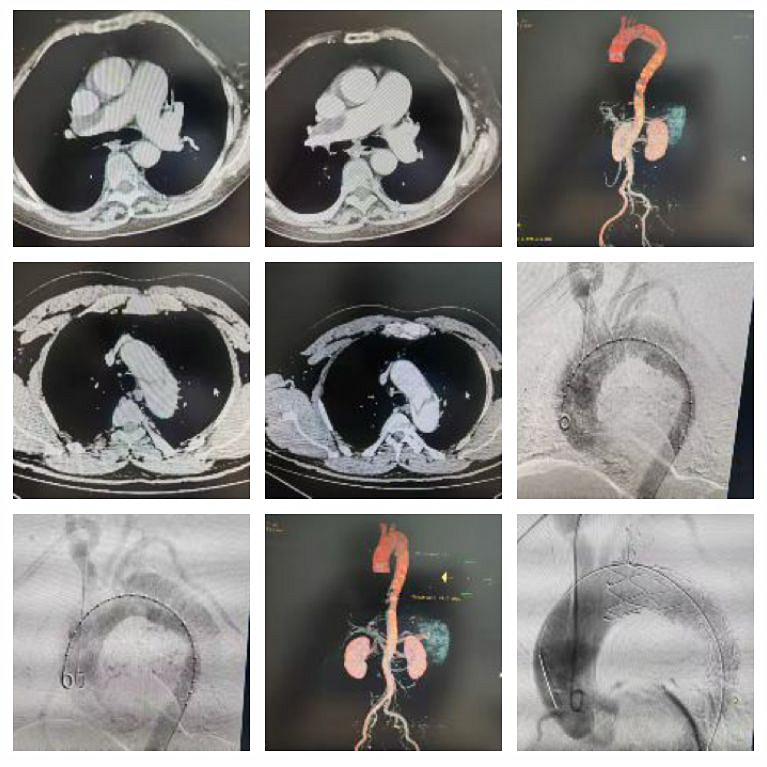

【医患故事】一位200斤合并心脏瓣膜病、心力衰竭的患者检查时发现腹腔干有一个巨大的“瘤体”----腹主动脉瘤,瘤腔最大直径为:55mm×100mm,瘤体极其扭曲,钙化严重,随时破裂。胸心血管外科黄小龙主任立即组织MDT进行讨论,制定手术方案,科室团队娴熟配合,为患者局麻下实施了腹主动脉瘤腔内隔绝术,成功将覆膜支架放到既定位置,术后造影复查腹腔分支动脉及髂动脉显影良好,血流正常,手术成功!